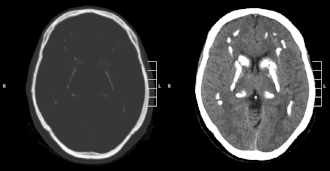

Descrito por primera vez en 1951, el síndrome de Fahr también conocido como ferrocalcinosis cerebro vascular, calcinosis de los núcleos del cerebro es una enfermedad que se presenta por calcificaciones masivas de núcleos de masa gris central, sin haber anomalía alguna en el metabolismo del calcio. Paralelamente, aparecen signos neurodegenerativos.

La constatación de las calcificaciones de la masa gris central es frecuente en muchas enfermedades. Cerca del 1 por ciento de los escáneres cerebrales muestran la presencia de calcificaciones de núcleos de masa gris central sobre todo después de los 60 años.[cita requerida] Esta constatación no se acompaña de un aumento de patología neurológia en estas personas.